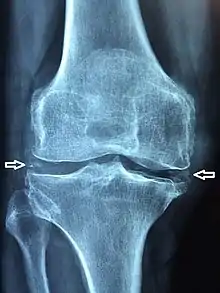

La chondrocalcinose articulaire (CCA) est une arthropathie microcristalline caractérisée par la précipitation de cristaux de pyrophosphate de calcium dihydraté (en) dans les tissus articulaires et périarticulaires. Elle entraîne la formation de calcification intra-articulaire sous la forme d'un liseré opaque fin, cernant les contours articulaires à quelques millimètres de l'os sous-chondral.

La chondrocalcinose est asymptomatique dans 25 % des cas. La découverte est radiologique. Les articulations les plus touchées sont les genoux, les poignets, et le bassin.

La forme pseudo-arthrosique représente 50 % des cas. Plus sévère que l’arthrose classique, la clinique est marquée par des arthralgies chroniques de types mécaniques et les radiographies montrent des signes classiques d’arthrose associés à des liserés typiques de la chondrocalcinose dans le cartilage et dans le fibrocartilage (les ménisques par exemple). Les articulations les plus souvent touchées sont la scapho-trapézienne, le poignet, les chevilles et les métacarpo-phalangiennes[3].